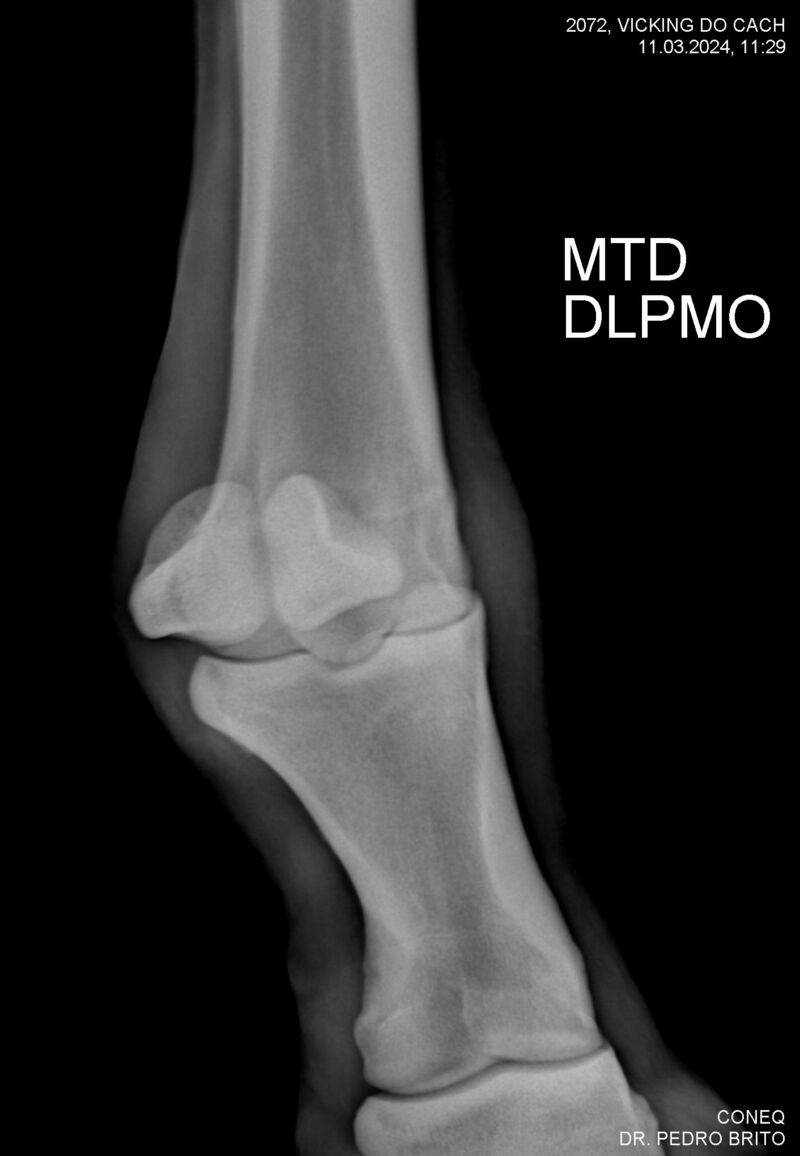

VIKING DO CACH